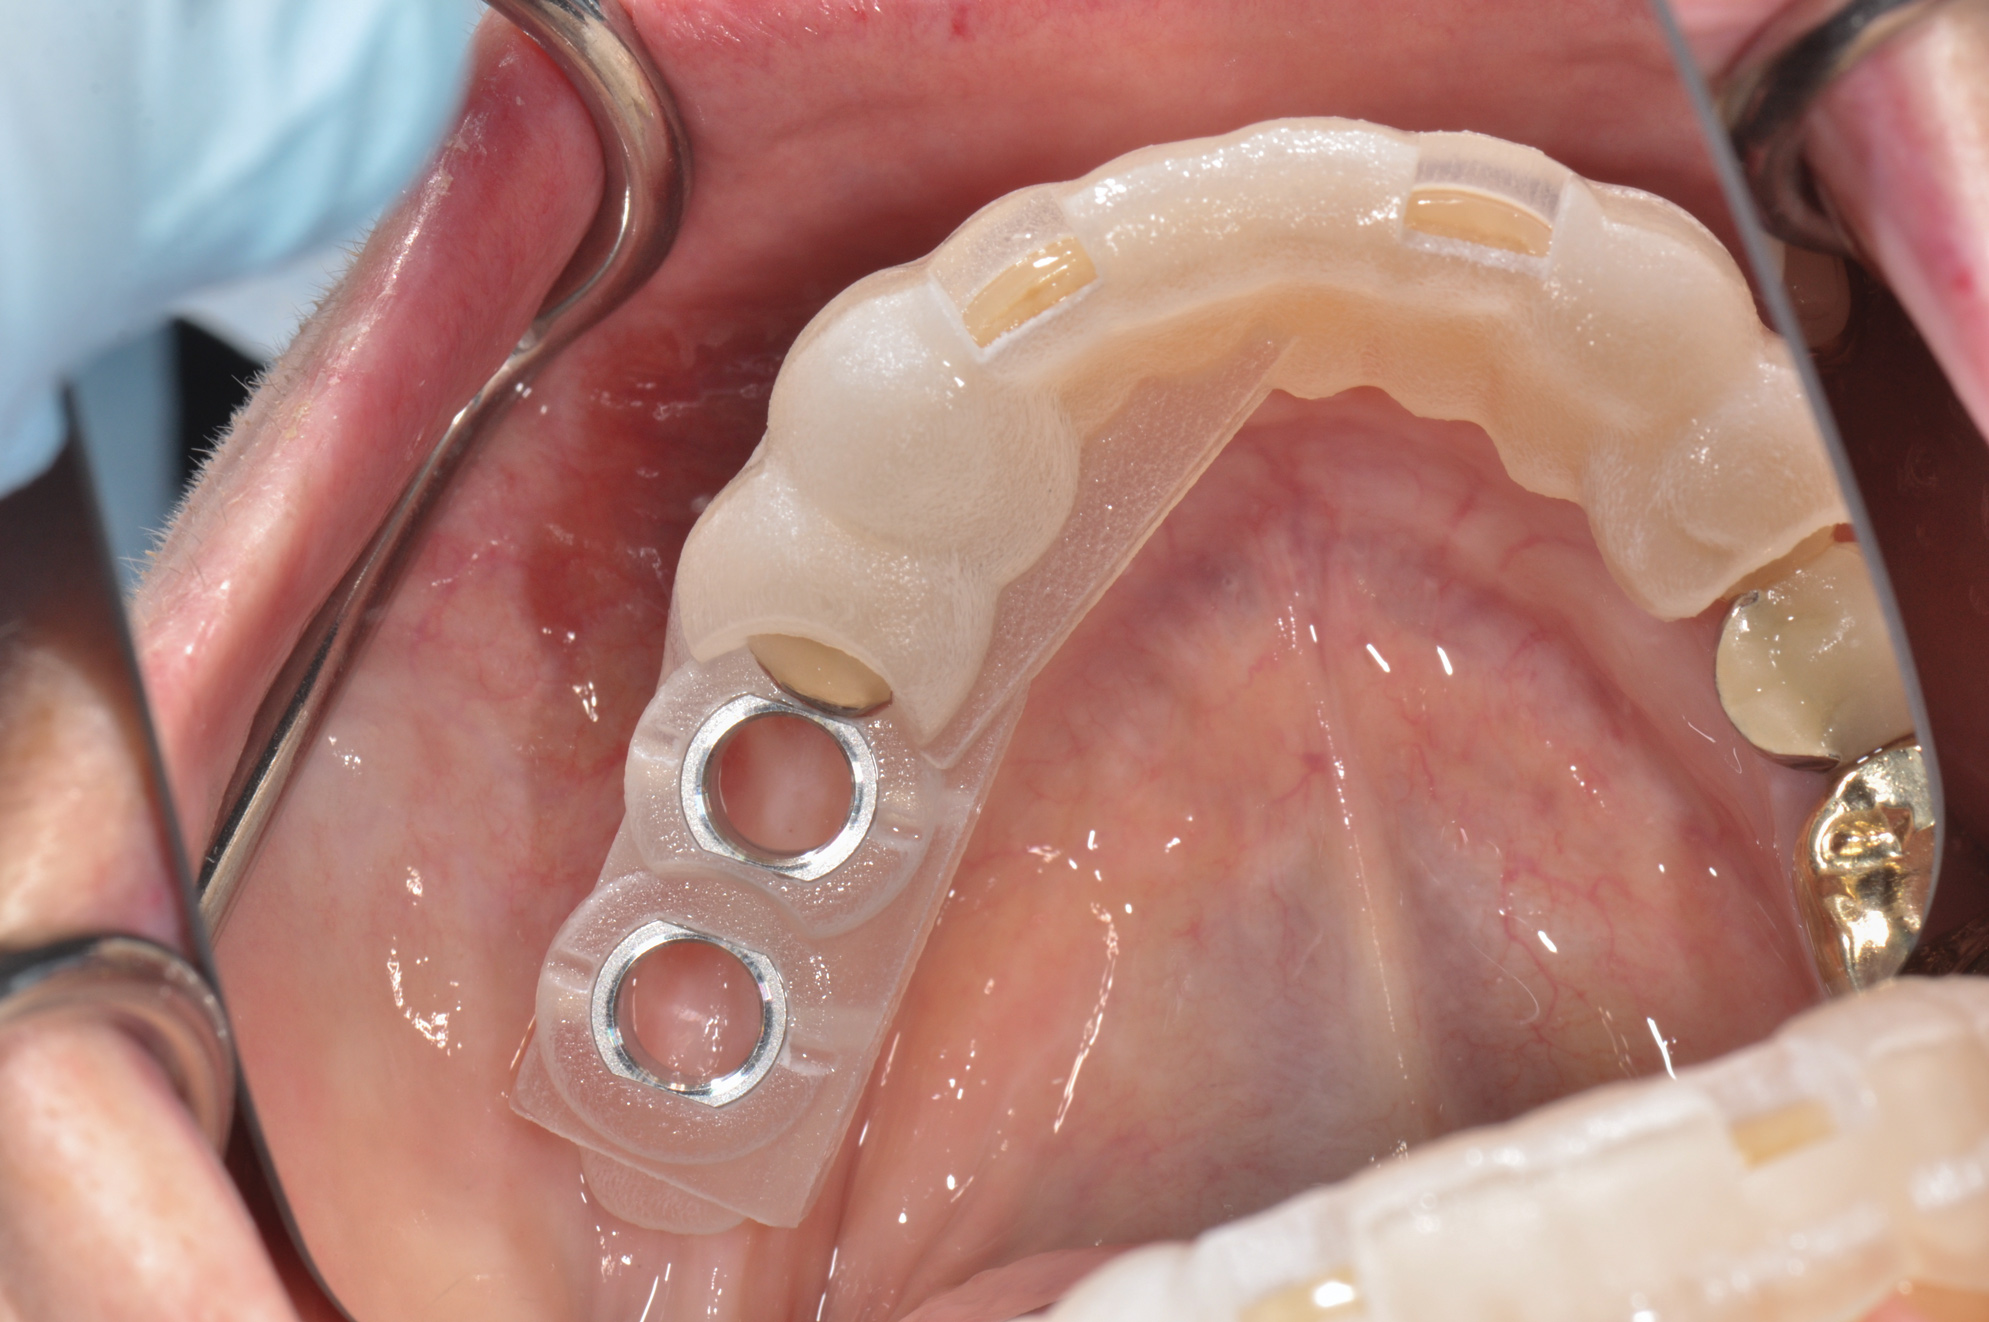

(26.) Guided-surgery template with inspection window.

Figure 26